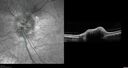

Chronic Myelogenous Leukemia and Diabetic Macular Edema56 views71 year old female with 3 months of vision loss and not feeling well. She has been bruising on her legs. Her vision was 20/100 in each eye with macular edema. She was treated with Avastin and her CBC was checked. She had a WBC of 267 thousand and was diagnosed with CML.Apr 20, 2024